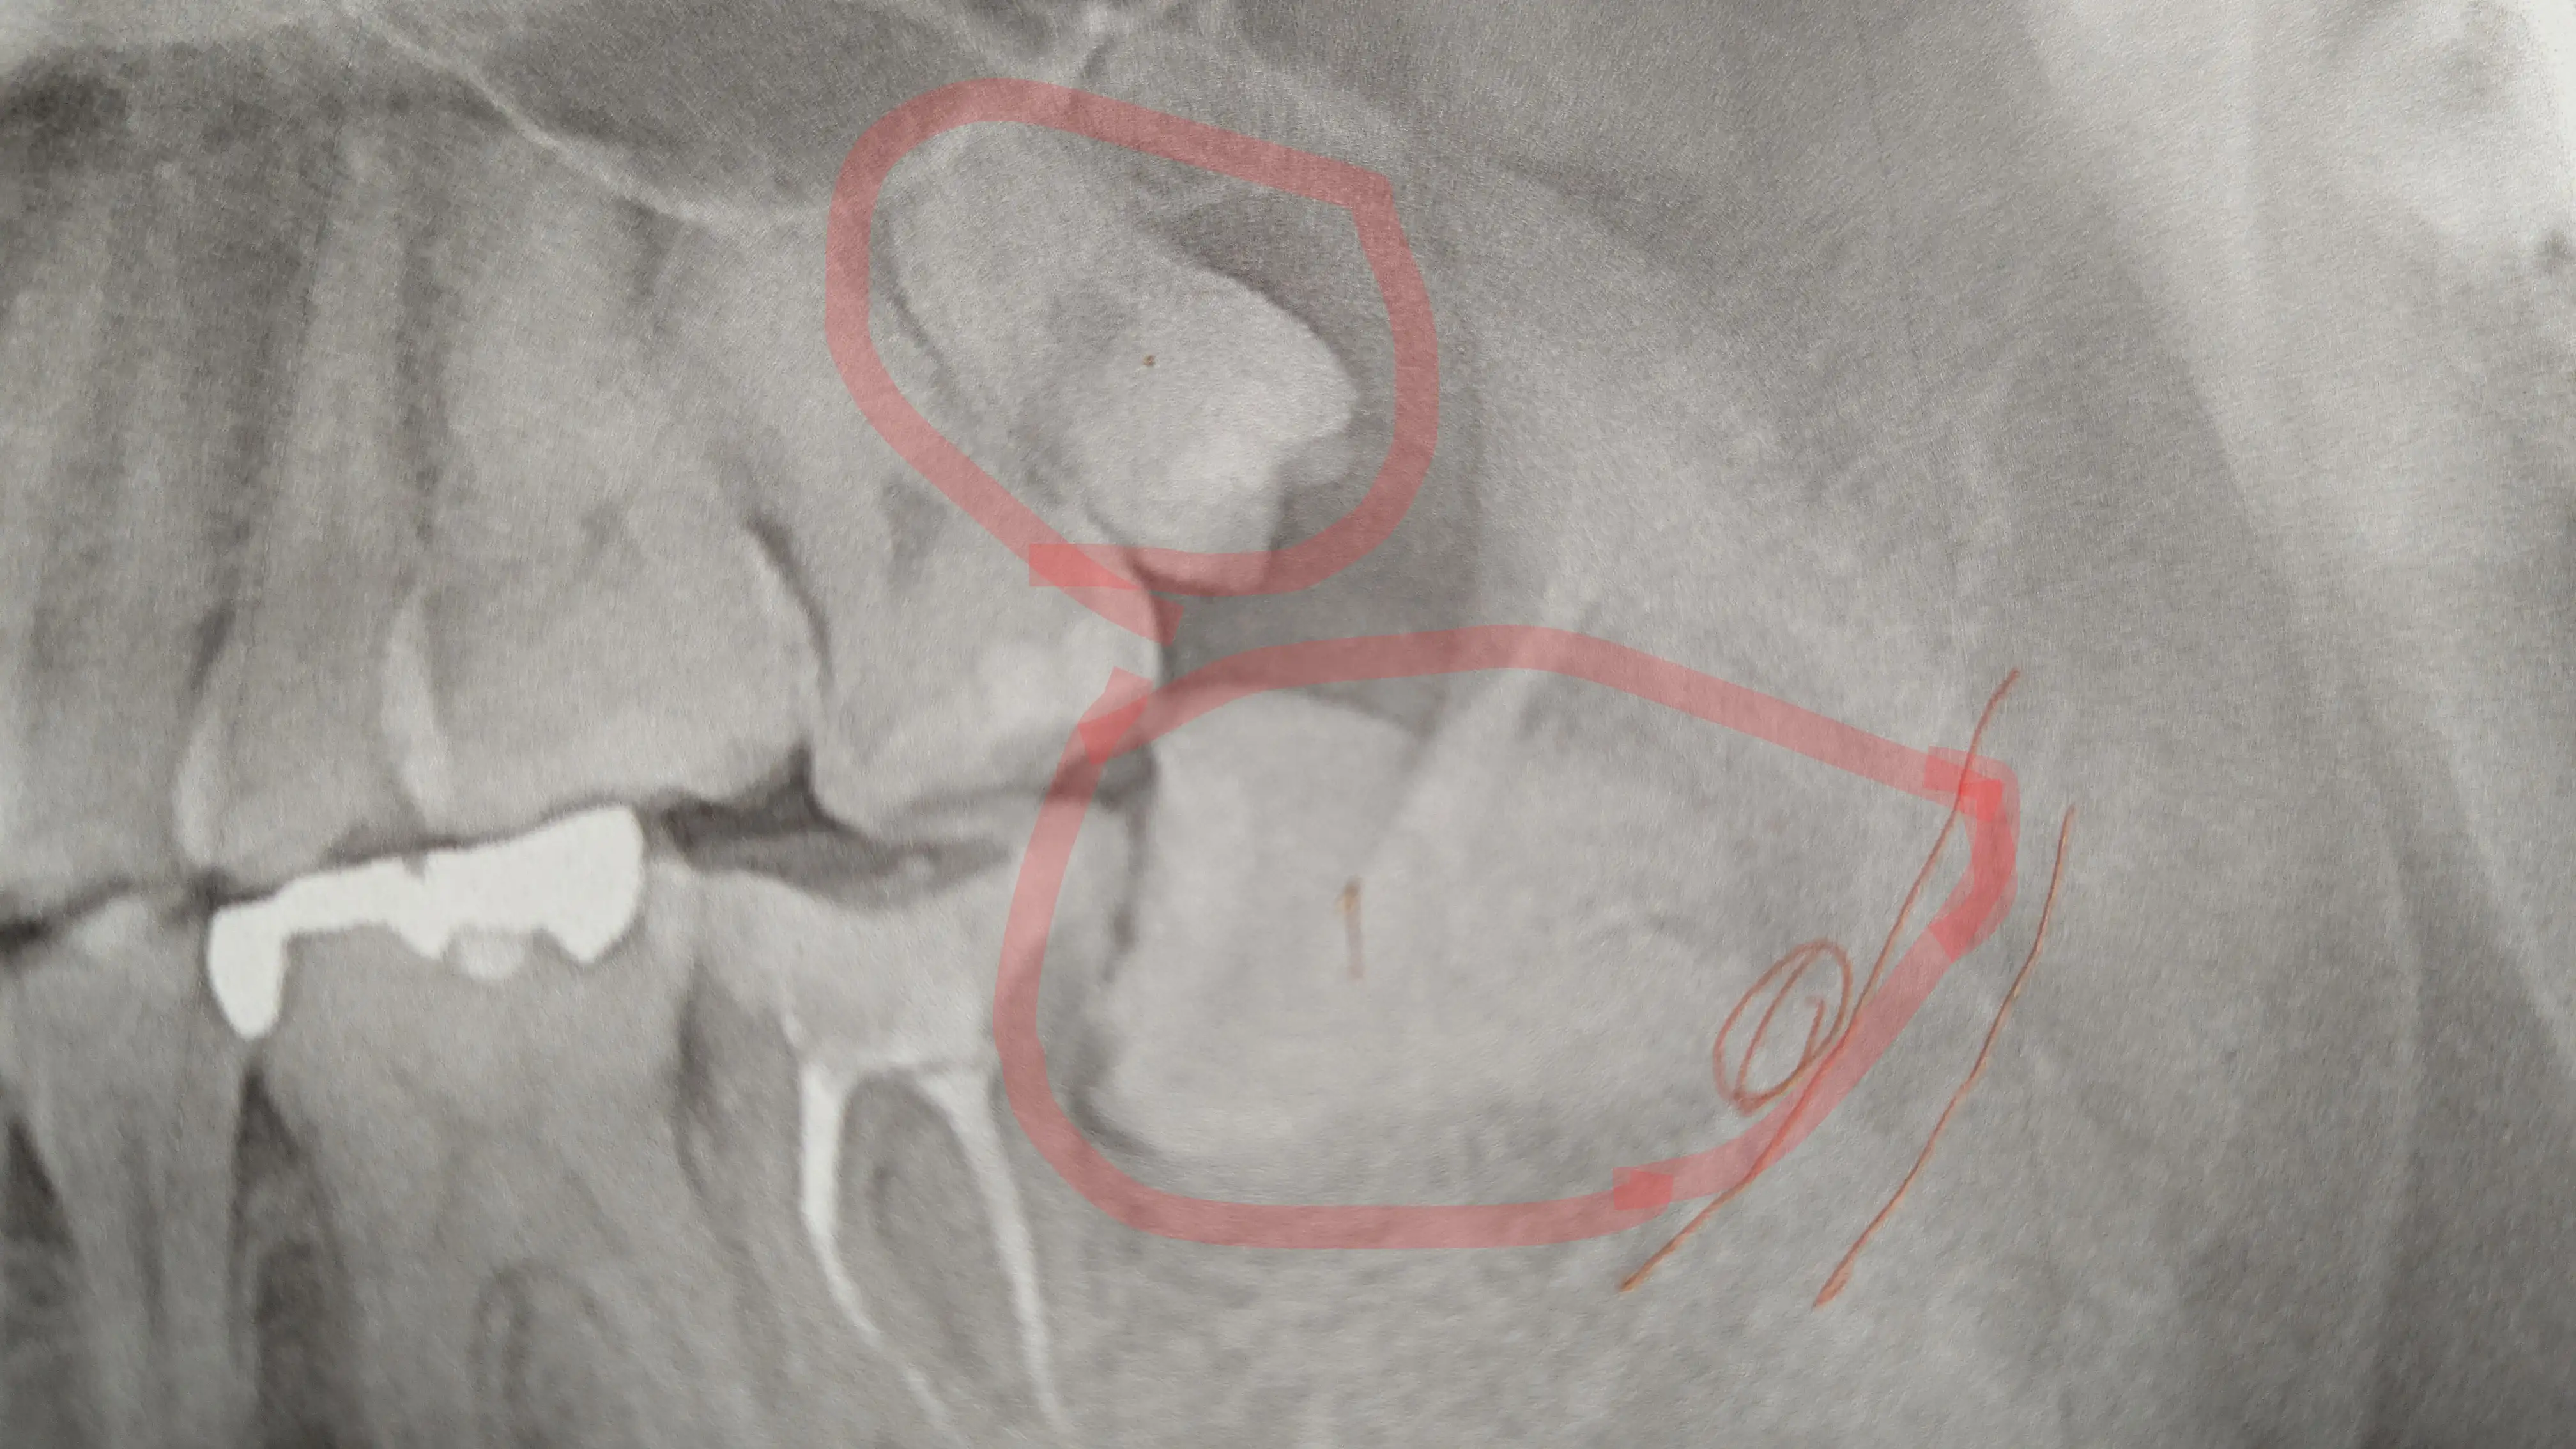

そんで午後に親知らずの抜歯に行った

最初の左下の親知らずに9割8分の時間を費やして次の上の歯は1分くらいで抜けてたと思う

何がどう行われていたかわからないけど下の歯は4つに割ったみたい

真っ直ぐ生えてたらすげー簡単に抜けるんだね

※フルカラーバージョンを見たい方はこちら

根っこが二股になってるのと割れた残骸が下の歯で大きいやつが上の歯